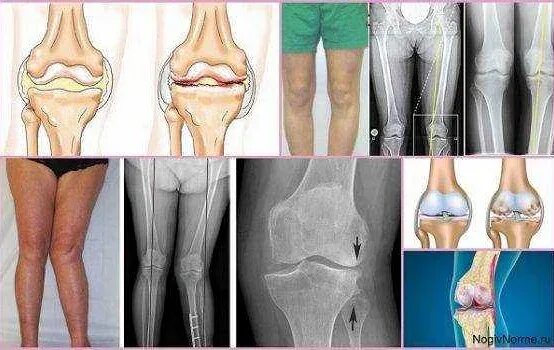

Деформирующий остеоартроз коленного сустава 1